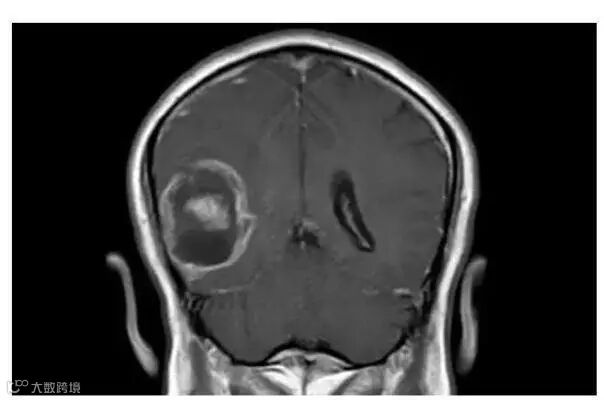

IBM沃森分析了脑肿瘤的基因组数据。图片来源:fiercebiotech

这项探索性的研究是在一位胶质母细胞瘤的患者身上进行的。胶质母细胞瘤是一种非常凶险的癌症,死亡率很高,确诊后的平均存活时间不到15个月。对于这样的癌症患者来说,时间是极其宝贵的,越早找到有针对性的治疗方案,就越有可能延长患者的生命。